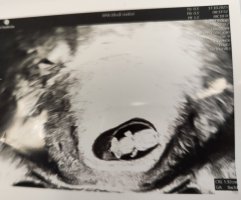

Jeg var på tidlig UL i dag, og da spurte hun først om vi var interessert i kjønn eller ville vente. Tror det varierer veldig fra sykehus til sykehus og de som jobber der. Vi fikk hvert fall vite at hun trodde det var jente, men kunne ikke si det helt sikkert - 13+0 i dag.Er det slik at de er skikkelig strenger på tidlig UL at de ikke ser på kjønnet?

Så jeg bestilte meg en privat UL, som jeg hadde tidligere i dag.